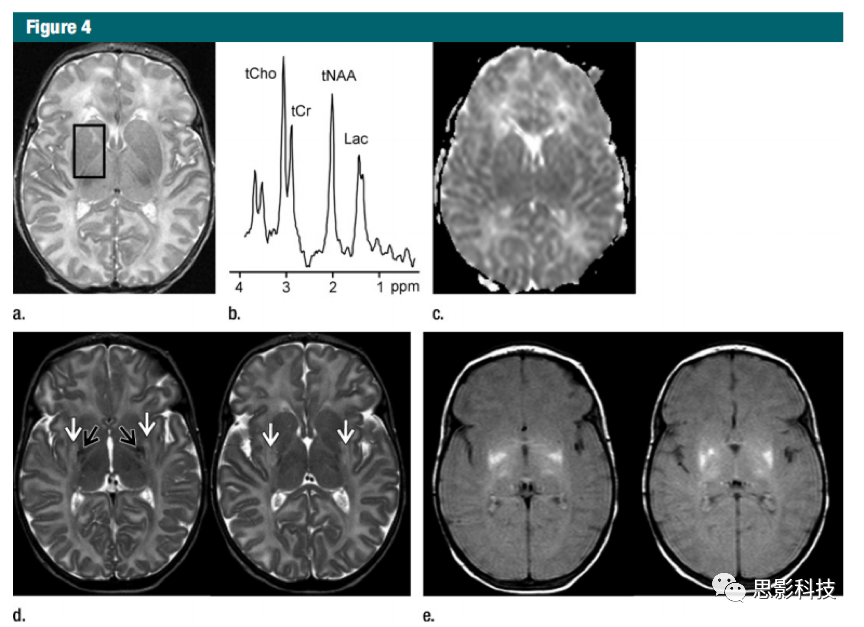

41H MR波譜學(xué)在新生兒圍產(chǎn)期缺氧缺血早期評估中的應(yīng)用。

在圍產(chǎn)期窒息后12小時(shí)(a-c)10天后(d, e)進(jìn)行MR成像。

a)軸向T2加權(quán)圖像未顯示信號異常,

b)從右基底神經(jīng)節(jié)獲得的頻譜(1.5 T, PRESS, 1500/288, 192 repetitions) 顯示Lac共振顯著增加,同時(shí)保留了tNAAtCrtCho共振。

c)具有軸向視擴(kuò)散系數(shù)圖的擴(kuò)散加權(quán)圖像(回波平面成像;30個(gè)方向;b=700 sec / mm2)顯示無擴(kuò)散異常。

d)軸向T2加權(quán)圖像顯示了殼核和丘腦中高(白色箭頭)和低(黑色箭頭)信號強(qiáng)度的區(qū)域,代表明顯的缺血性出血性病變。

e)軸向質(zhì)子密度圖像顯示出明顯的病變擴(kuò)展。